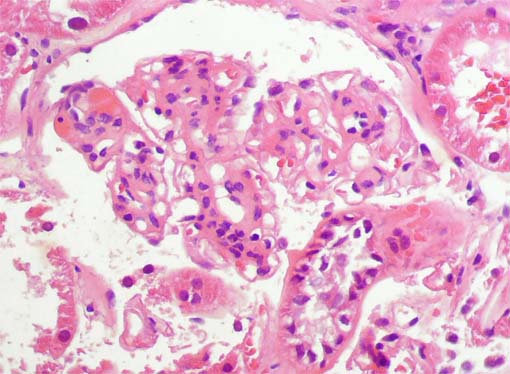

Figura 3.

H&E, X400.